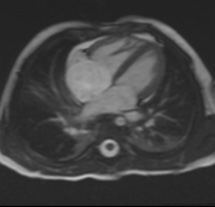

Description: Congenital heart diseases are heart problems that children are born with. These diseases range from simple to complex and many require surgery or other procedures.

Why MRI: Heart MRI is used to capture images in all types of congenital heart disease and at all ages. It can be used to help determine if and what type of surgery might be needed. It can also be used after surgery for routine follow up and check if there are any complications.

Heart MRI captures images of the heart and blood vessels to help see exactly the location and size of the structures. Sometimes 3D models are made to help see everything. Heart MRI can also measure flow in blood vessels and measure how well the heart muscle is pumping.

Images: ASD, 3D aorta, Flow in single ventricle